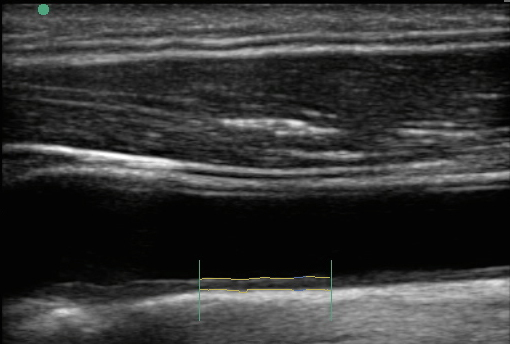

Image : carotide, mesure EIM

EIM - Épaisseur intima-media